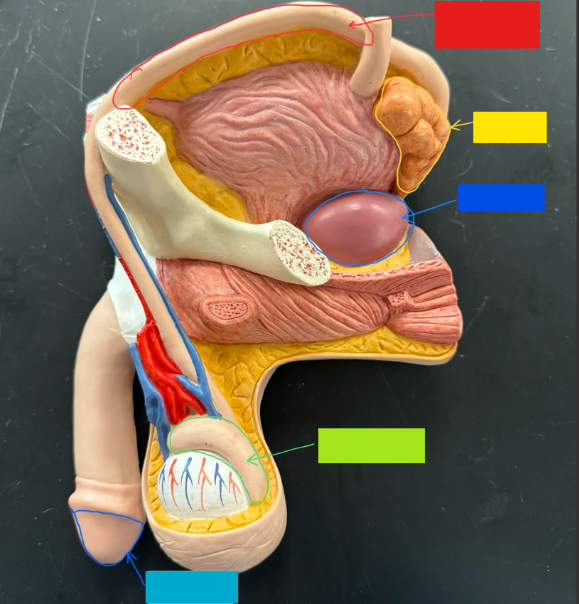

What is the name of the red box?

Ureter

What is the name of the yellow box?

Seminal vesicle

What is the name of the blue box?

Prostate

What is the name of the light green box?

Epididymis

What is the name of the light blue box?

Prepuce